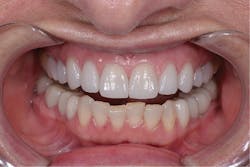

The enamel was selectively acid etched with Select HV Etch (Bisco). This is a 35% high-viscosity phosphoric acid etchant available with benzalkonium chloride, an antimicrobial agent that does not slump. The teeth were then treated with All-Bond Universal (Bisco), which is a light-cure bonding agent that is compatible with light, self and dual-cured cementation materials. The manufacturer’s instructions were followed.5 The eCement was then placed in the crowns and cured for 2 to 3 seconds only. The excess cement was removed, and the final cure was completed. The teeth were seated two at a time, starting with Nos. 8 and 9. After all crowns were seated, final cleanup was completed, occlusion was verified, and minor esthetic correction was completed (figures 7 and 8).

Figure 8: Anterior smile view of the patient’s final restoration